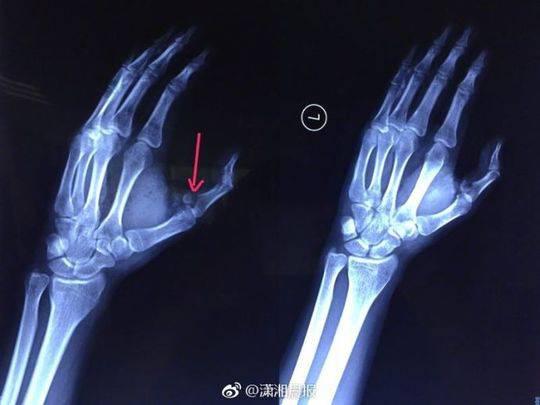

劇烈的疼痛讓小袁發(fā)出慘叫,家人聞訊趕來一看,只見他的傷口血流不止,受傷的左手也動彈不得,隨即將他送往湖南省人民醫(yī)院急診一科就診,醫(yī)生為其傷口進行了緊急處理。X 光檢查發(fā)現(xiàn),小袁的左手拇指近節(jié)指骨骨折,需進行手術(shù)固定,于是將他收入創(chuàng)傷骨病科病房。